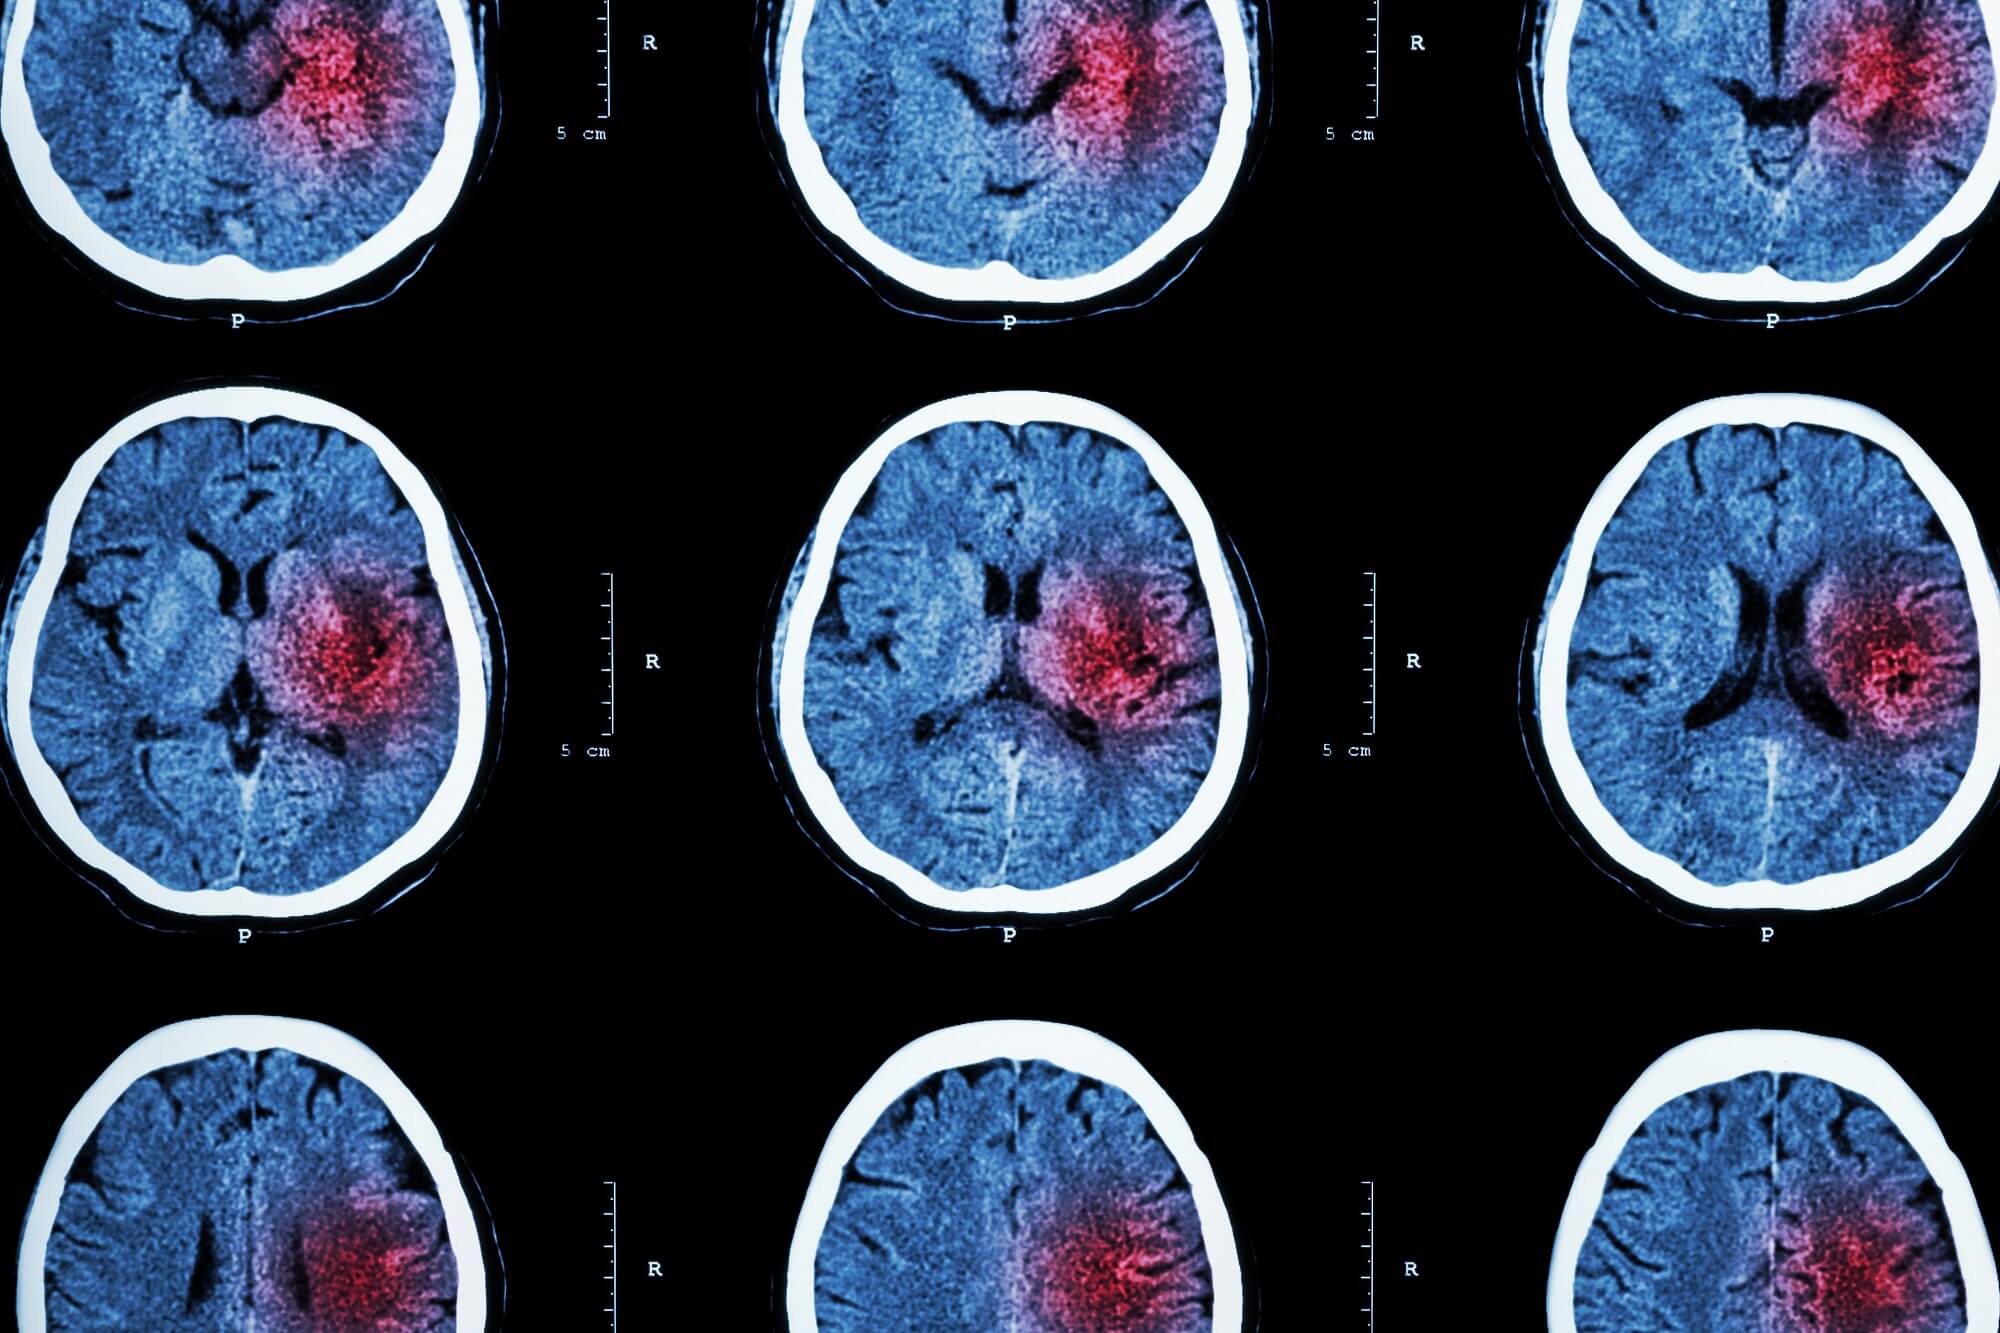

Hyperbaric Oxygen Therapy Anoxic Brain Injury . cessation of cerebral circulation leads to depletion of oxygen stores within 20 seconds and manifests as loss of consciousness. Hyperbaric oxygen therapy (hbo2) aims to address ischemia resulting from brain injury by. this comprehensive review demonstrates that hbo 2 has the potential to be the first significant treatment in the. hyperbaric oxygen therapy (hbot) is the administration of high concentrations of oxygen within a pressurized chamber. hyperbaric oxygen therapy (hbo2) has recently been shown to have neurotherapeutic effects in patients.